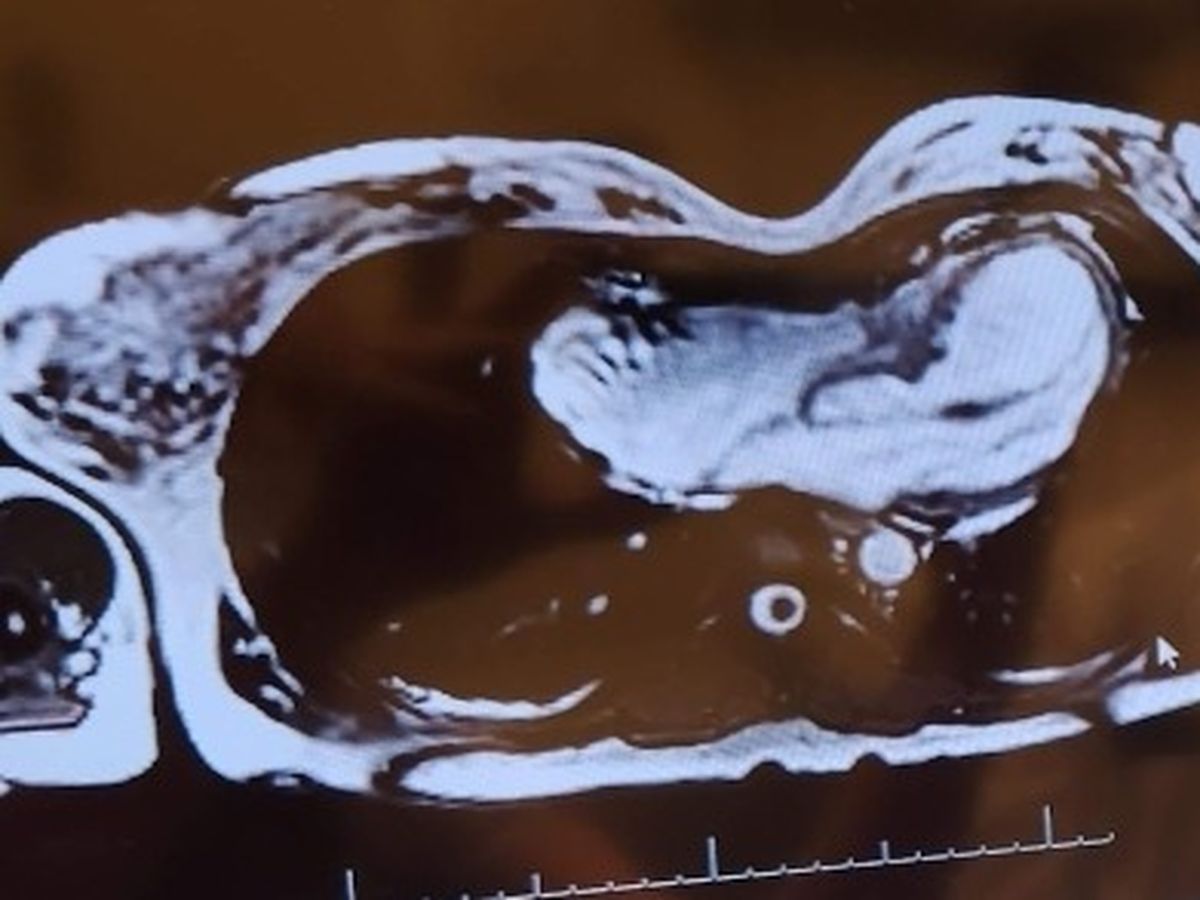

I will be out of work for at least 6 weeks while I recover from having a Nuss Procedure. I will need help covering bills and basic living expenses during that time.